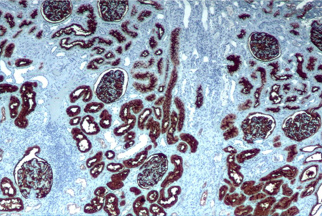

Anatomia patológica é uma especialidade médica dedicada ao estudo das alterações estruturais e funcionais das células, tecidos e órgãos causadas por doenças. Os profissionais dessa área, conhecidos como anatomopatologistas ou patologistas, utilizam microscópios e técnicas laboratoriais avançadas para examinar amostras de tecidos obtidas através de biópsias, cirurgias ou autópsias.

Anatomia Patológica Biópsias e Espécimes Cirúrgicos

Colorações Especiais (específicas)

Exames Imunohistoquímicos